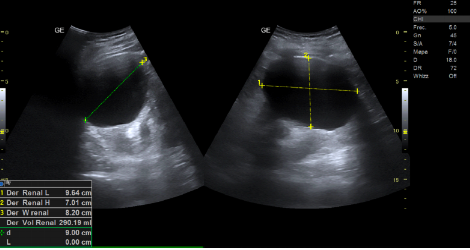

- Ecografía clínica renovesical: Vejiga sin lesiones ocupantes de espacio, sin residuo postmiccional, próstata de tamaño aumentado (56 cc). Ambos riñones con quistes corticales simples, de hasta 9,6 cm en el riñón izquierdo. Sistema excretor derecho no dilatado. Leve-moderada dilatación pielocalicial izquierda. No se evidencian imágenes ecográficas sugestivas de litiasis en pelvis renal.

- Resonancia magnética renal con contraste: hidronefrosis grado II izquierda, secundaria a litiasis obstructiva de 5 mm localizada en el tercio inferior del uréter, inmediatamente caudal al cruce con los vasos ilíacos. Quistes sinusales y simples corticales bilaterales, el mayor de 9,4 cm de eje craneocaudal en el polo inferior del riñón izquierdo. Resto sin alteraciones significativas.